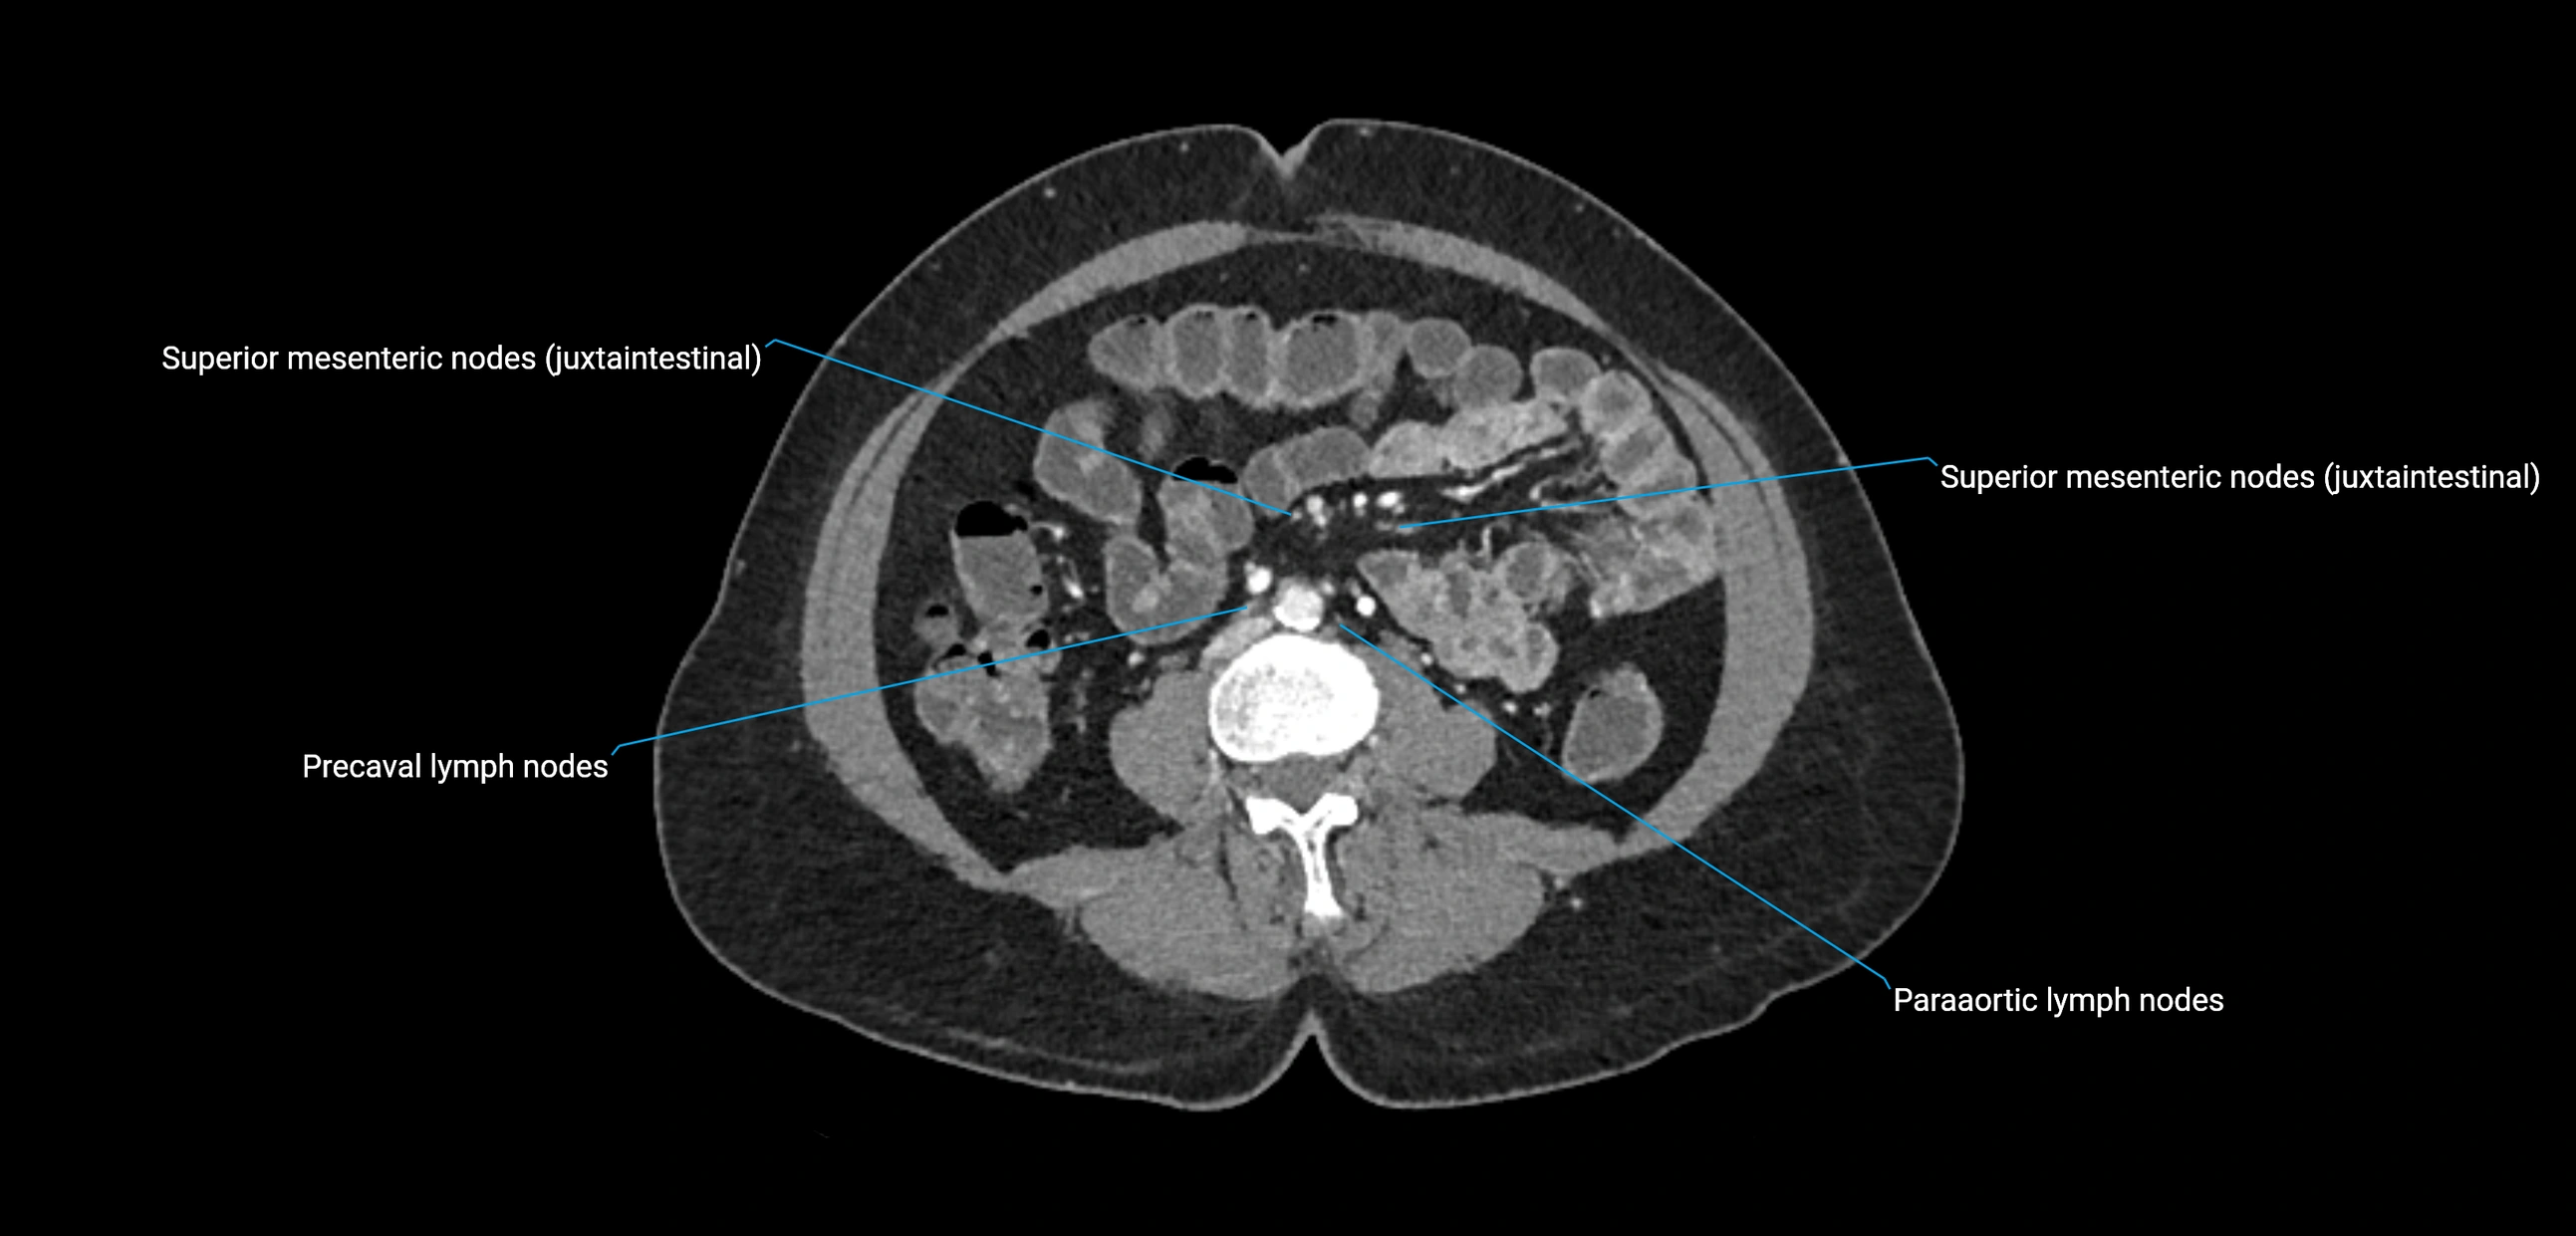

CT image

image